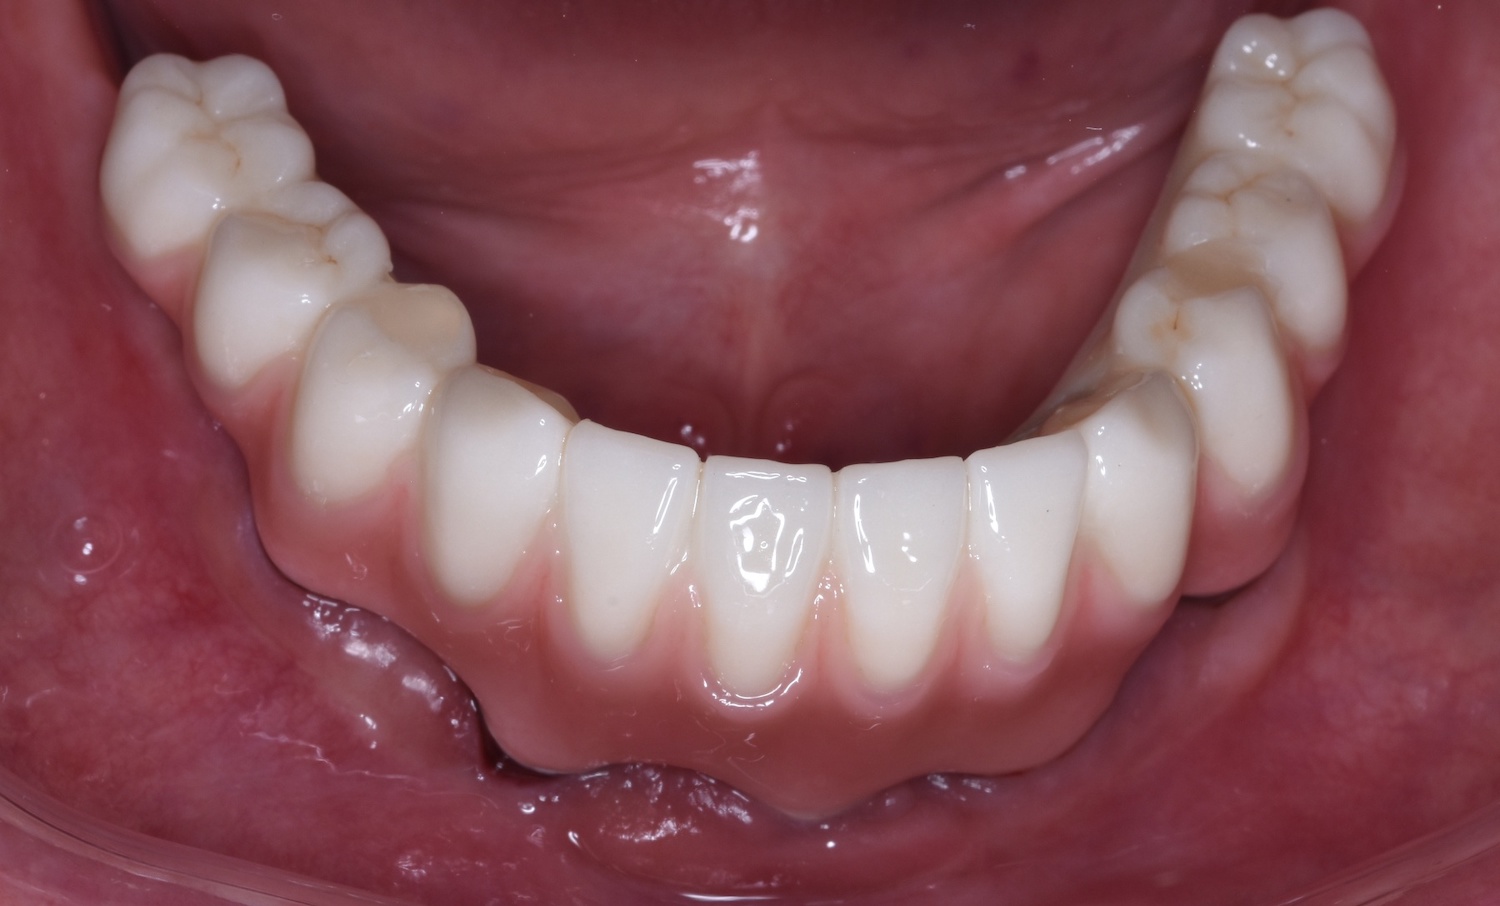

2. Zkouška tvaru a přesnosti v definitivním anatomickém tvaru pomocí bílého resinu nebo frézovaného či tištěného PMMA ✅

Zkouška přesnosti a tvaru pomocí PMMA

Pomocí PMMA je konečný výsledek Branemarku kompletně předem vyzkoušený a odsouhlasený lékařem i pacientem.

Při odevzdávání tedy nehrozí žádné překvapení.